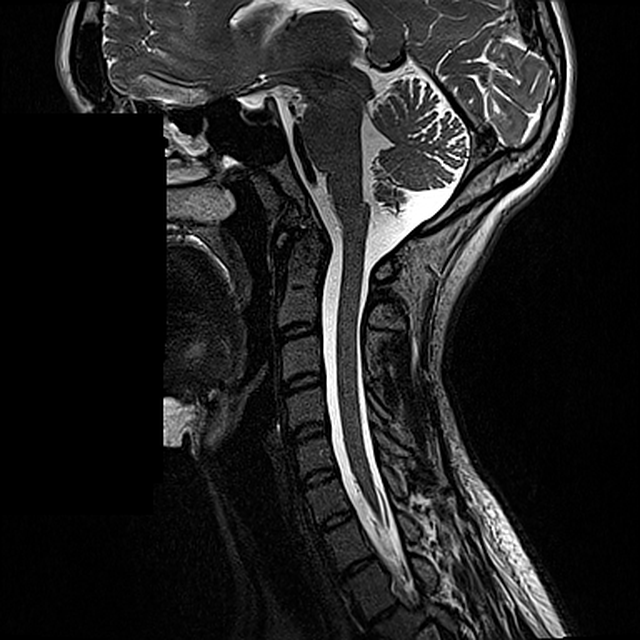

Kaularangan T2-sagittaalinen anatomia

Kaularangan T2-kuvasarja, jossa rakenteiden pisteitä ja kuvauksia voi korjata suoraan sivulla.

Kaularanka Sagittal T2 Aktiivinen

Taso 33 / 64 keskitaso

vasen/lateraalinen keskitaso oikea/lateraalinen